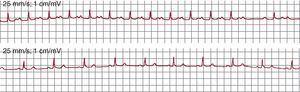

Diagnóstico electrocardiográficoTaquicardia auricular focalLa taquicardia auricular focal (TAF) se define como un ritmo auricular rápido, regular, no originado en el nódulo sinusal, con ondas P de morfología estable en el ECG y que precisa sólo de estructuras auriculares para su mantenimiento1 (Figura 1). La alternancia de ondas P y líneas de base estables indica que la taquicardia así definida en el ECG sea de mecanismo focal (TAF) con periodos de reposo entre descargas del foco (Figura 2), pero hay excepciones a esta regla.

Figura 1. Electrocardiograma y registros endocárdicos de taquicardia auricular focal y aleteo auricular típico en un mismo paciente. Los paneles inferiores muestran registros endocárdicos bipolares de la aurícula derecha anterior (Ta-A4 de arriba abajo), el istmo cavotricuspídeo, la aurícula derecha septal de abajo arriba (S4-Tp) y el seno coronario de proximal a distal (SC1-SC5). El sombreado azul muestra la porción del ciclo de la taquicardia cubierta por la activación, < 50% en la taquicardia auricular focal y el 100% en el aleteo auricular, incluso considerando sólo registros de aurícula derecha. AA: aleteo auricular; ICT: istmo cavotricuspídeo; OVF: onda de velocidad de flujo; SC: seno coronario; TAF: taquicardia auricular focal.

Aleteo auricularSe ha denominado clásicamente aleteo auricular (AA) o flutter a una taquicardia auricular de muy alta frecuencia (240-350 lpm), con ondas auriculares que producen una oscilación continua sin línea de base plana1 (Figura 1). Este patrón indicaría actividad continua durante todo el ciclo de activación auricular, como en el caso del AA típico (común) (Figura 3), pero puede haber un patrón de ondulación continua en TAF rápidas, en las que la duración de la onda P es muy próxima a la longitud de ciclo (LC).